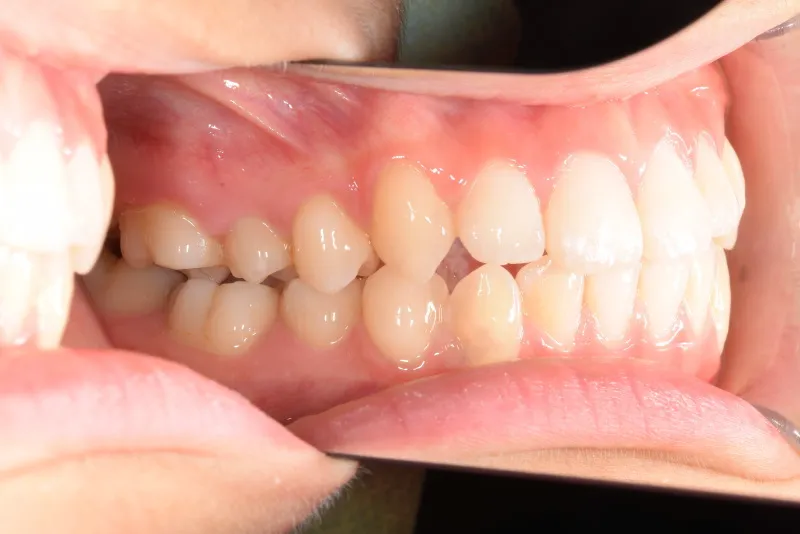

初診時年齢 小学校3年生 (女性) 主訴 出っ歯・前歯がゆがんでいる

診断名 叢生・上顎前突 装置名

状態 永久歯が生える隙間がない(叢生)

ガタガタ・でこぼこに生えている(叢生)

出っ歯(口元が出ている/上顎前突)

出っ歯と前歯のゆがみを主訴に来院されました。

低学年時は取り外しの装置を使用し、高学年になってからは見えにくい固定式の装置を使用して治療しました。

治療回数48回、7年2ヶ月の治療期間で矯正治療を終了しました。

主訴が改善され、ご満足頂きました。